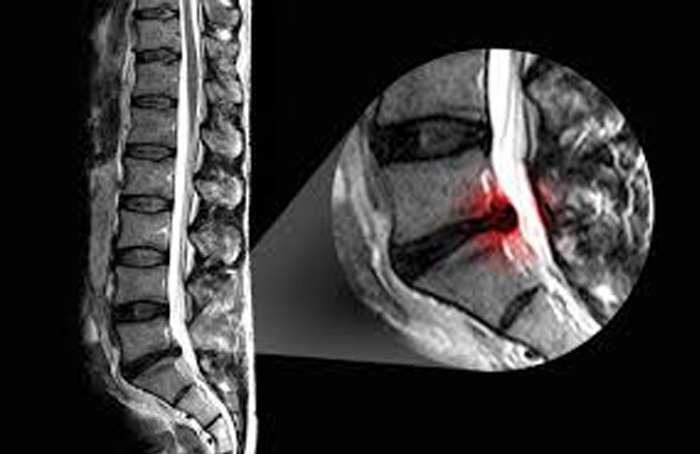

درمان انواع کمر درد ، سیاتیک ، دیسک های اسیب دیده و پاره با روش MDT

روش تشخیص مکانیکی و درمان مکنزی MDT

McKenzie method is Mechanical Diagnosis and Therapy به عنوان یک روش تایید شده بین المللی جهت ارزیابی ، تشخیص و درمان آسیب و پارگی دیسکهای مهره ای ،درد ها و مشکلات ستون فقرات ...